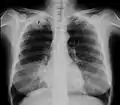

Radiografía de tórax que muestra un tumor de Pancoast (etiquetado como P, carcinoma pulmonar de células grandes, pulmón derecho), de una mujer fumadora de 47 años. -